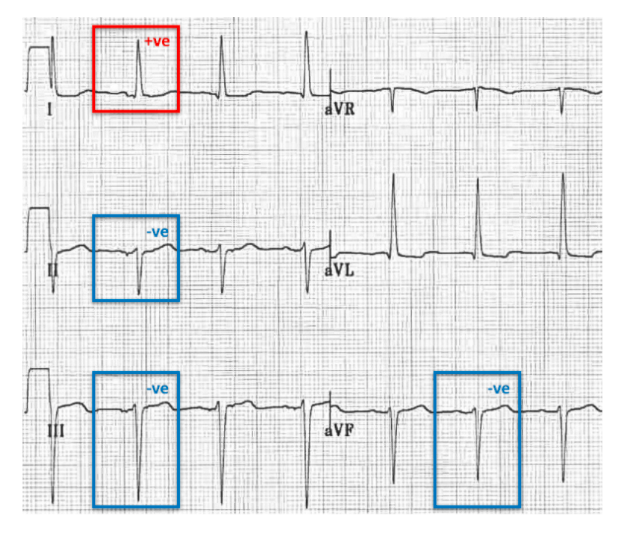

What does an anterior division hemiblock cause on an ECG?

Left axis deviation

What does a posterior division hemiblock cause on an ECG?

Right axis deviation